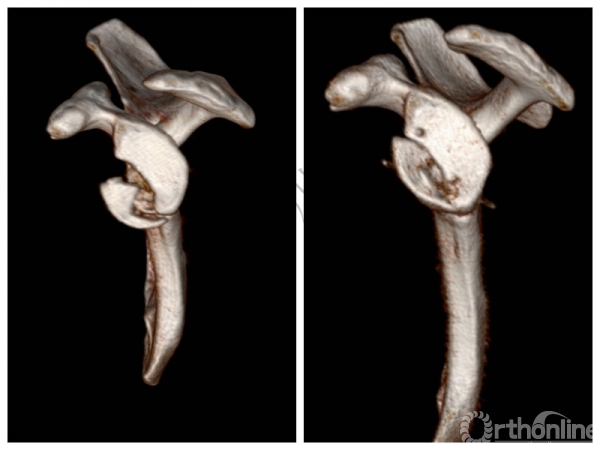

三、病例特点——复杂多病合一,进行科内讨论会诊

科室内部病例讨论后确认诊断,计划手术治疗!

3. 术前诊断、手术方案与术式

1.影像学评估